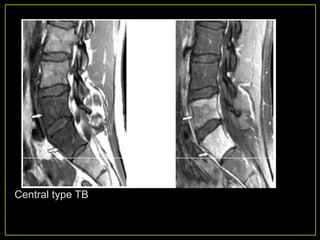

3. Central Lesions :

• Centred on the vertebral body.

Batson‟s venous plexus or posterior

vertebral artery.

• Disc not involved.

• Vertebral collapse occur - vertebra plana

appearance.

• MR - signal abnormality of the vertebral body

with preservation of the disc.

• DD: Appearance is indistinguishable from that of

lymphoma or metastasis.

Central type TB